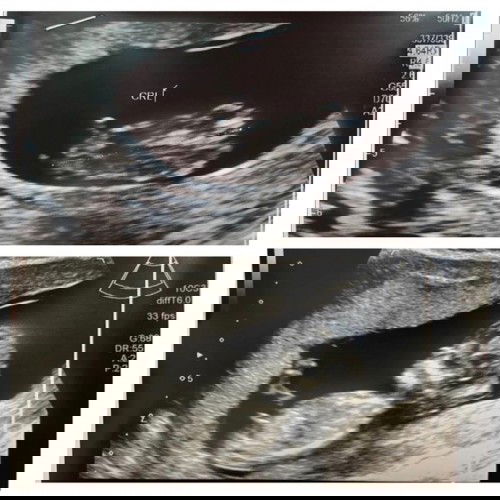

Boy or girl?

i'd say girl the nub looks parallel